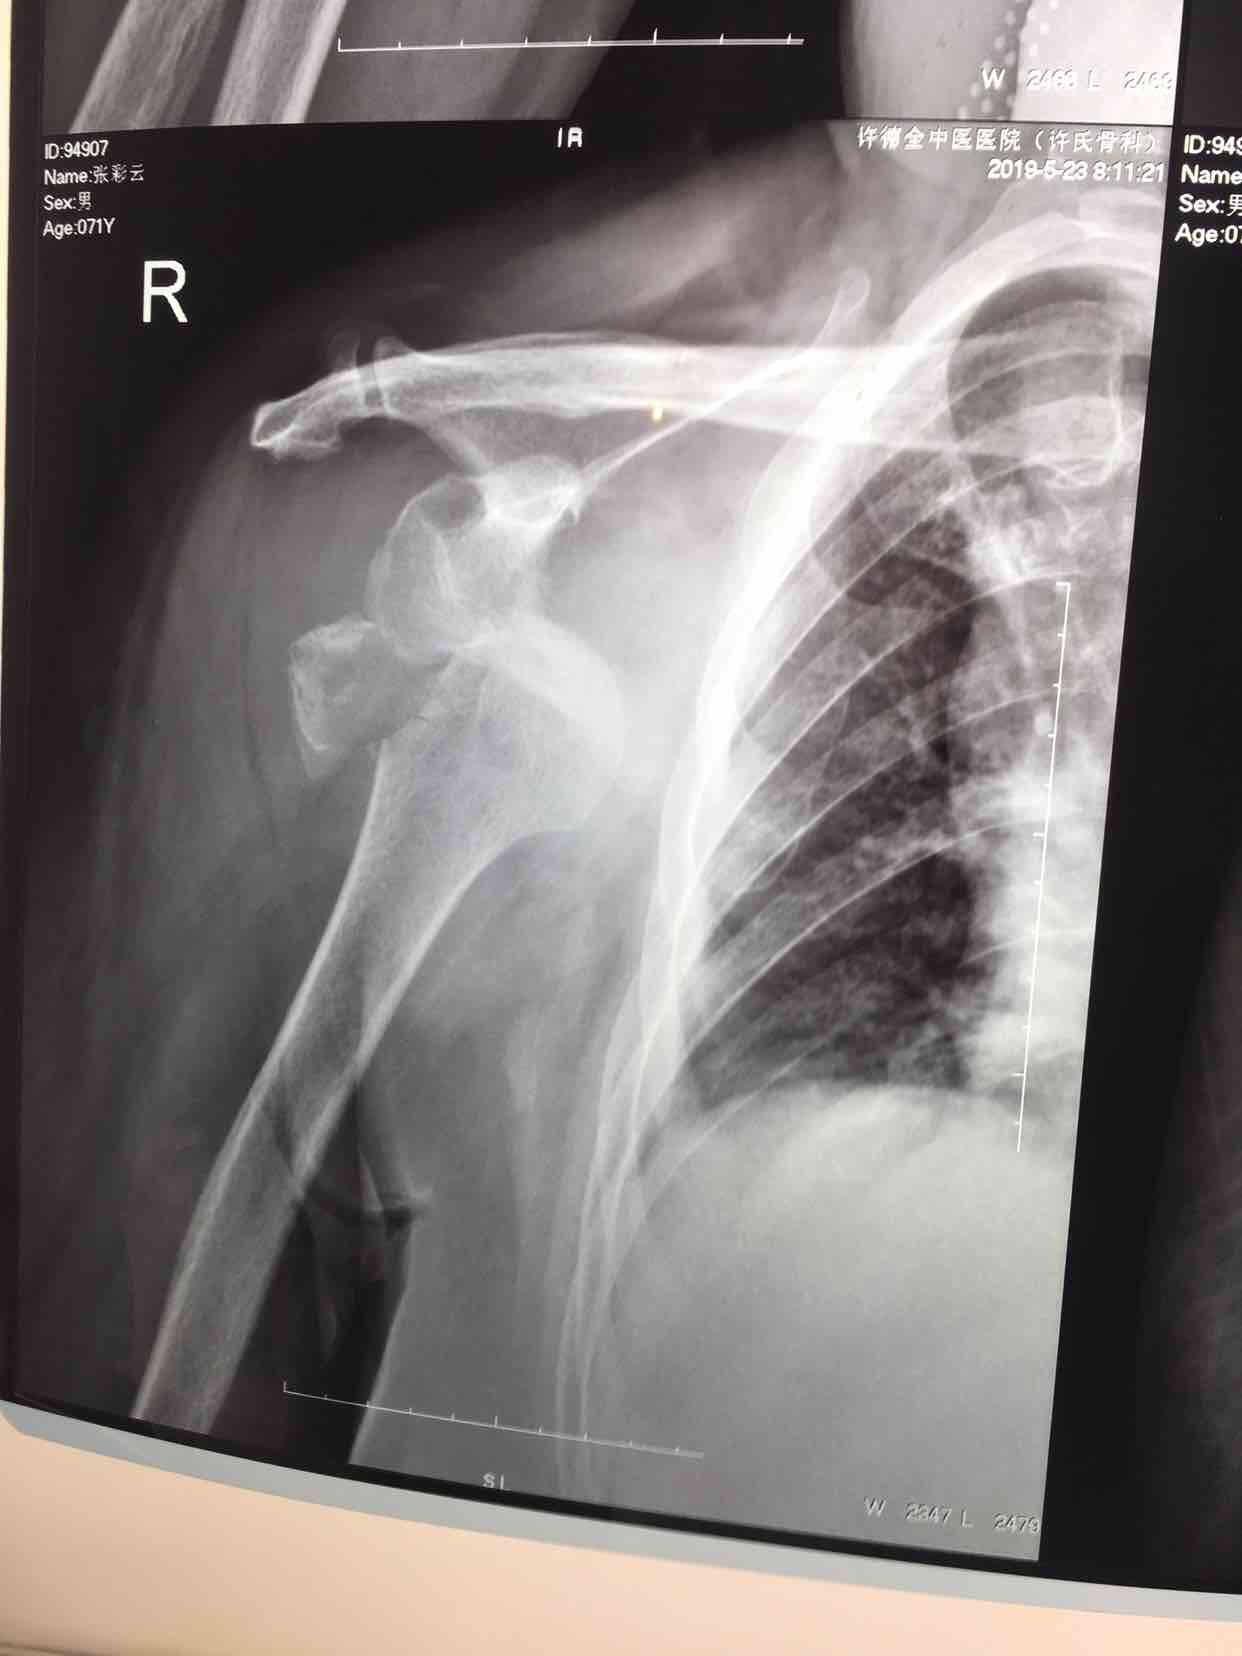

肩关节脱位并大结节骨折(切复内固定)

摔伤后右肩部肿痛,活动受限1天入院。既往患有冠心病数年,无特殊不良嗜好。

生命体征平稳,心肺腹未见异常。右肩部肿胀明显,局部皮色青紫淤瘢,皮温基本正常,搭肩试验阳性,关节盂空虚,肩关节活动受限,远端血运感觉正常。

诊断肩关节脱位并大结节骨折在臂丛麻醉下行切复内固定术,术后外展架固定,抗炎,消肿等处理。